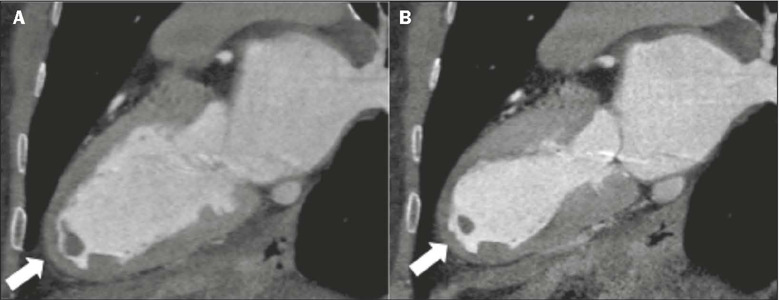

Takotsubo cardiomyopathy is an important differential diagnosis for acute chest pain. Imaging tests, such as ventriculography, echocardiography, computed tomography of the heart, and cardiac magnetic resonance, are valuable tools for diagnostic confirmation in this context. This study reviews the literature and exemplifies the spectrum of typical and atypical cardiac magnetic resonance findings in this disease, on the basis of the experience of our facility. Recognition of these characteristics underscores the roles that radiologists and cardiologists play in the care of patients with acute chest pain, enabling an accurate diagnosis and appropriate treatment.